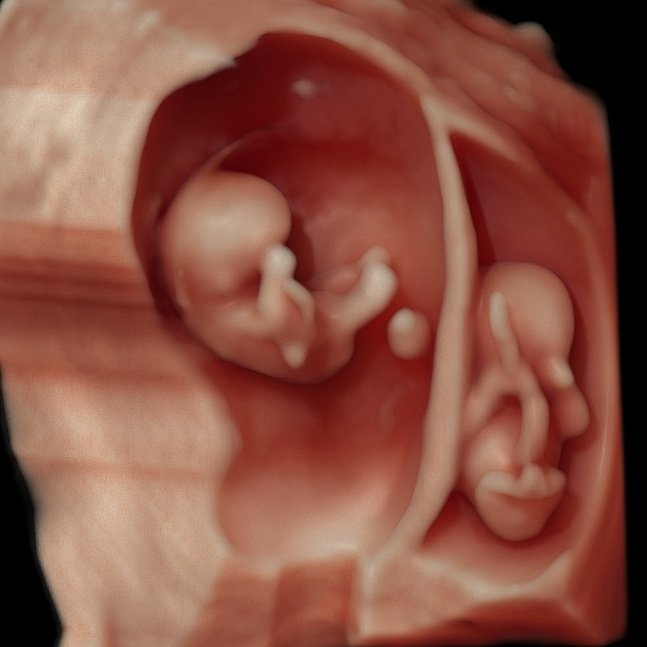

In 3&4D de baby zien blijft natuurlijk heel erg bijzonder. Samen met de familie kijken op wie de kleine lijkt en wat er allemaal in je buik gebeurd is zo speciaal. Het maakt het allemaal nog echter, omdat het soms zo moeilijk te bevatten is dat er zo’n klein wonder in je groeit. De mooiste periode om de baby in 3&4D te bekijken is tussen de 27 en 30 weken zwangerschap.

Ook na de 30 weken maken we vaak nog hele mooie beelden, het is natuurlijk ook gewoon een beetje geluk hebben. Dus mocht je twijfelen kom dan altijd gewoon proberen, mocht het niet lukken en denken we dat het ook niet meer gaat lukken, dan betaal je alleen de even spieken echo!

Korte Pretecho 3/4D

Vanaf 20 weken, 15 min, inclusief zwart/wit foto en 2 kleurenfoto's afgedrukt. We maken de mooiste scherpe foto's van voornamelijk het gezichtje. Denk aan profiel, vooraanzicht, maar we kijken ook live mee in de buik en zien lachjes, gaapjes en soms wordt er zelfs gezwaaid! Een eerste echte ontmoeting met de baby in de buik.

Uitgebreide Pretecho 3/4D

Vanaf 20 weken, 25 min inclusief zwart/wit foto’s en 4 kleurenfoto’s afgedrukt. We maken de mooiste scherpe foto's van voornamelijk het gezichtje. Denk aan profiel, vooraanzicht, maar we kijken ook live mee in de buik en zien lachjes, gaapjes en soms wordt er zelfs gezwaaid! Een eerste echte ontmoeting met de baby in de buik. We luisteren naar het hartje en vertellen je alles over de ligging, placenta en anatomie.